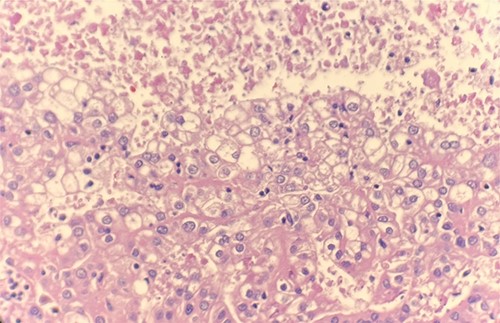

Microscopic examination revealed that clear cell RCC (Fig. 1), papillary RCC type 1 (Fig. 2), and papillary RCC type 2 (Fig. 3) were present in the right kidney, and papillary RCC type 2 was present in both kidneys. Immunostaining showed that tumor cells were positive for alpha-methyacyl-CoA racemase (Fig. 4), CD10, CK7, and vimentin, and negative for CD117.

Immunohistochemical stain reveals that tumor cells are positive for alpha-methyacyl-CoA racemase. IHC stain 40x.